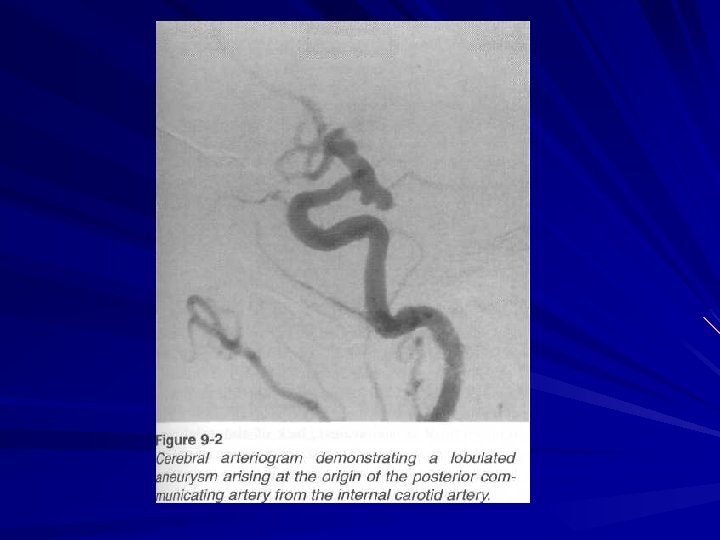

Aneurysm

Diagnostics In blood usually leucocytosis, related lymphopenia, hyperglycemia (up to 8 – 10 mmole per liter) In liquor high pressure during lubar puncture a great number of erythrocytes are found On eye fundus – retinal hemorrhages, hypertonic angioretinopathy and Salus symptoms are observed At echoencephaloscopy there is dislocation of middle structures on 6 – 7 sm to the healthy side At angiography - aneurysm, dislocation of blood vessels, to find out zone “without vessels“ CT and MRI find out hyperdensive focuses.

Subarachnoid hemorrhage Aetiologic factors: Aneurysmatic ( 50 – 62 % ) – aneurysm rupture. Hypertensive ( at hypertension ) Atherosclerotic ( 15 % ) Traumatic ( 5 – 6 % ) Infectious – toxic ( 8. 5 % ) Blastomatose ( at tumors ) Pathohemic ( at blood diseases ) Cryptogenic ( 4 – 4. 8 % )